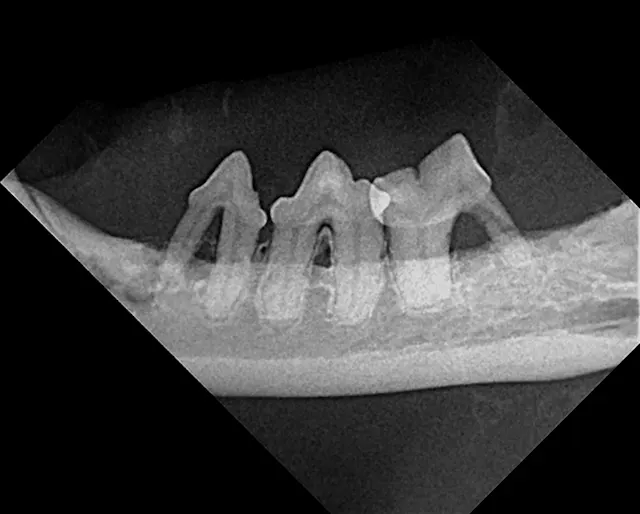

Close-up, lateral image of right cat maxilla

FIGURE 1

Significant alveolar and labial/buccal mucositis, likely associated with advanced periodontal disease, in a 5-year-old neutered male domestic shorthair cat. Radiographs are recommended to evaluate for any changes (eg, tooth resorption).